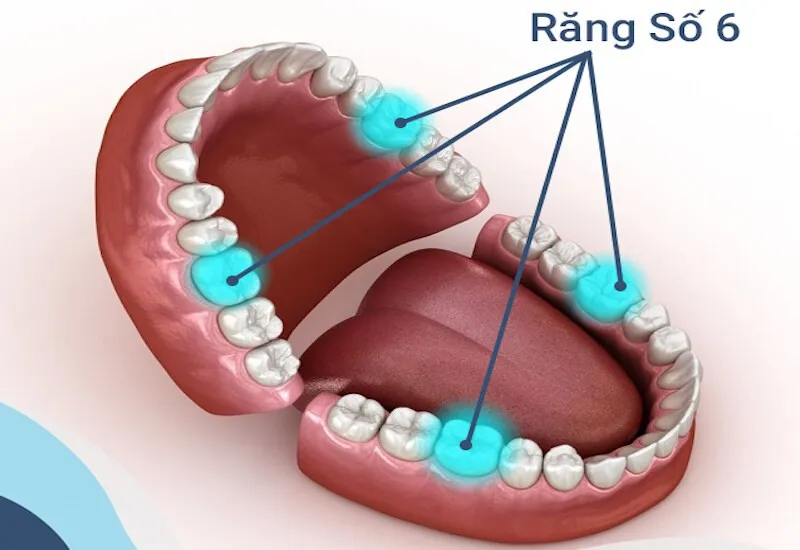

Răng hàm số 6, hay còn gọi là răng cối lớn thứ nhất, là một trong những răng quan trọng trong việc nhai và nghiền thức ăn.